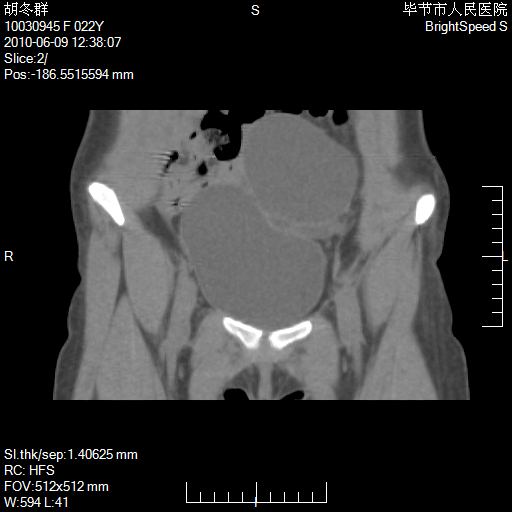

患者23岁,发现腹部包块3月。

左侧卵巢囊腺瘤或囊腺癌

盆腔内囊性占位性病变;考虑左侧卵巢囊腺瘤。

有分隔、壁薄,支持考虑左侧卵巢囊腺瘤。

左侧卵巢浆液性囊腺瘤。

支持考虑左侧卵巢囊腺瘤;宫腔积液。

有分隔、壁薄,支持考虑左侧卵巢囊腺瘤。排尿后,膀胱缩小,由于重力作用,肿块下移就到了膀胱位置,很好理解。